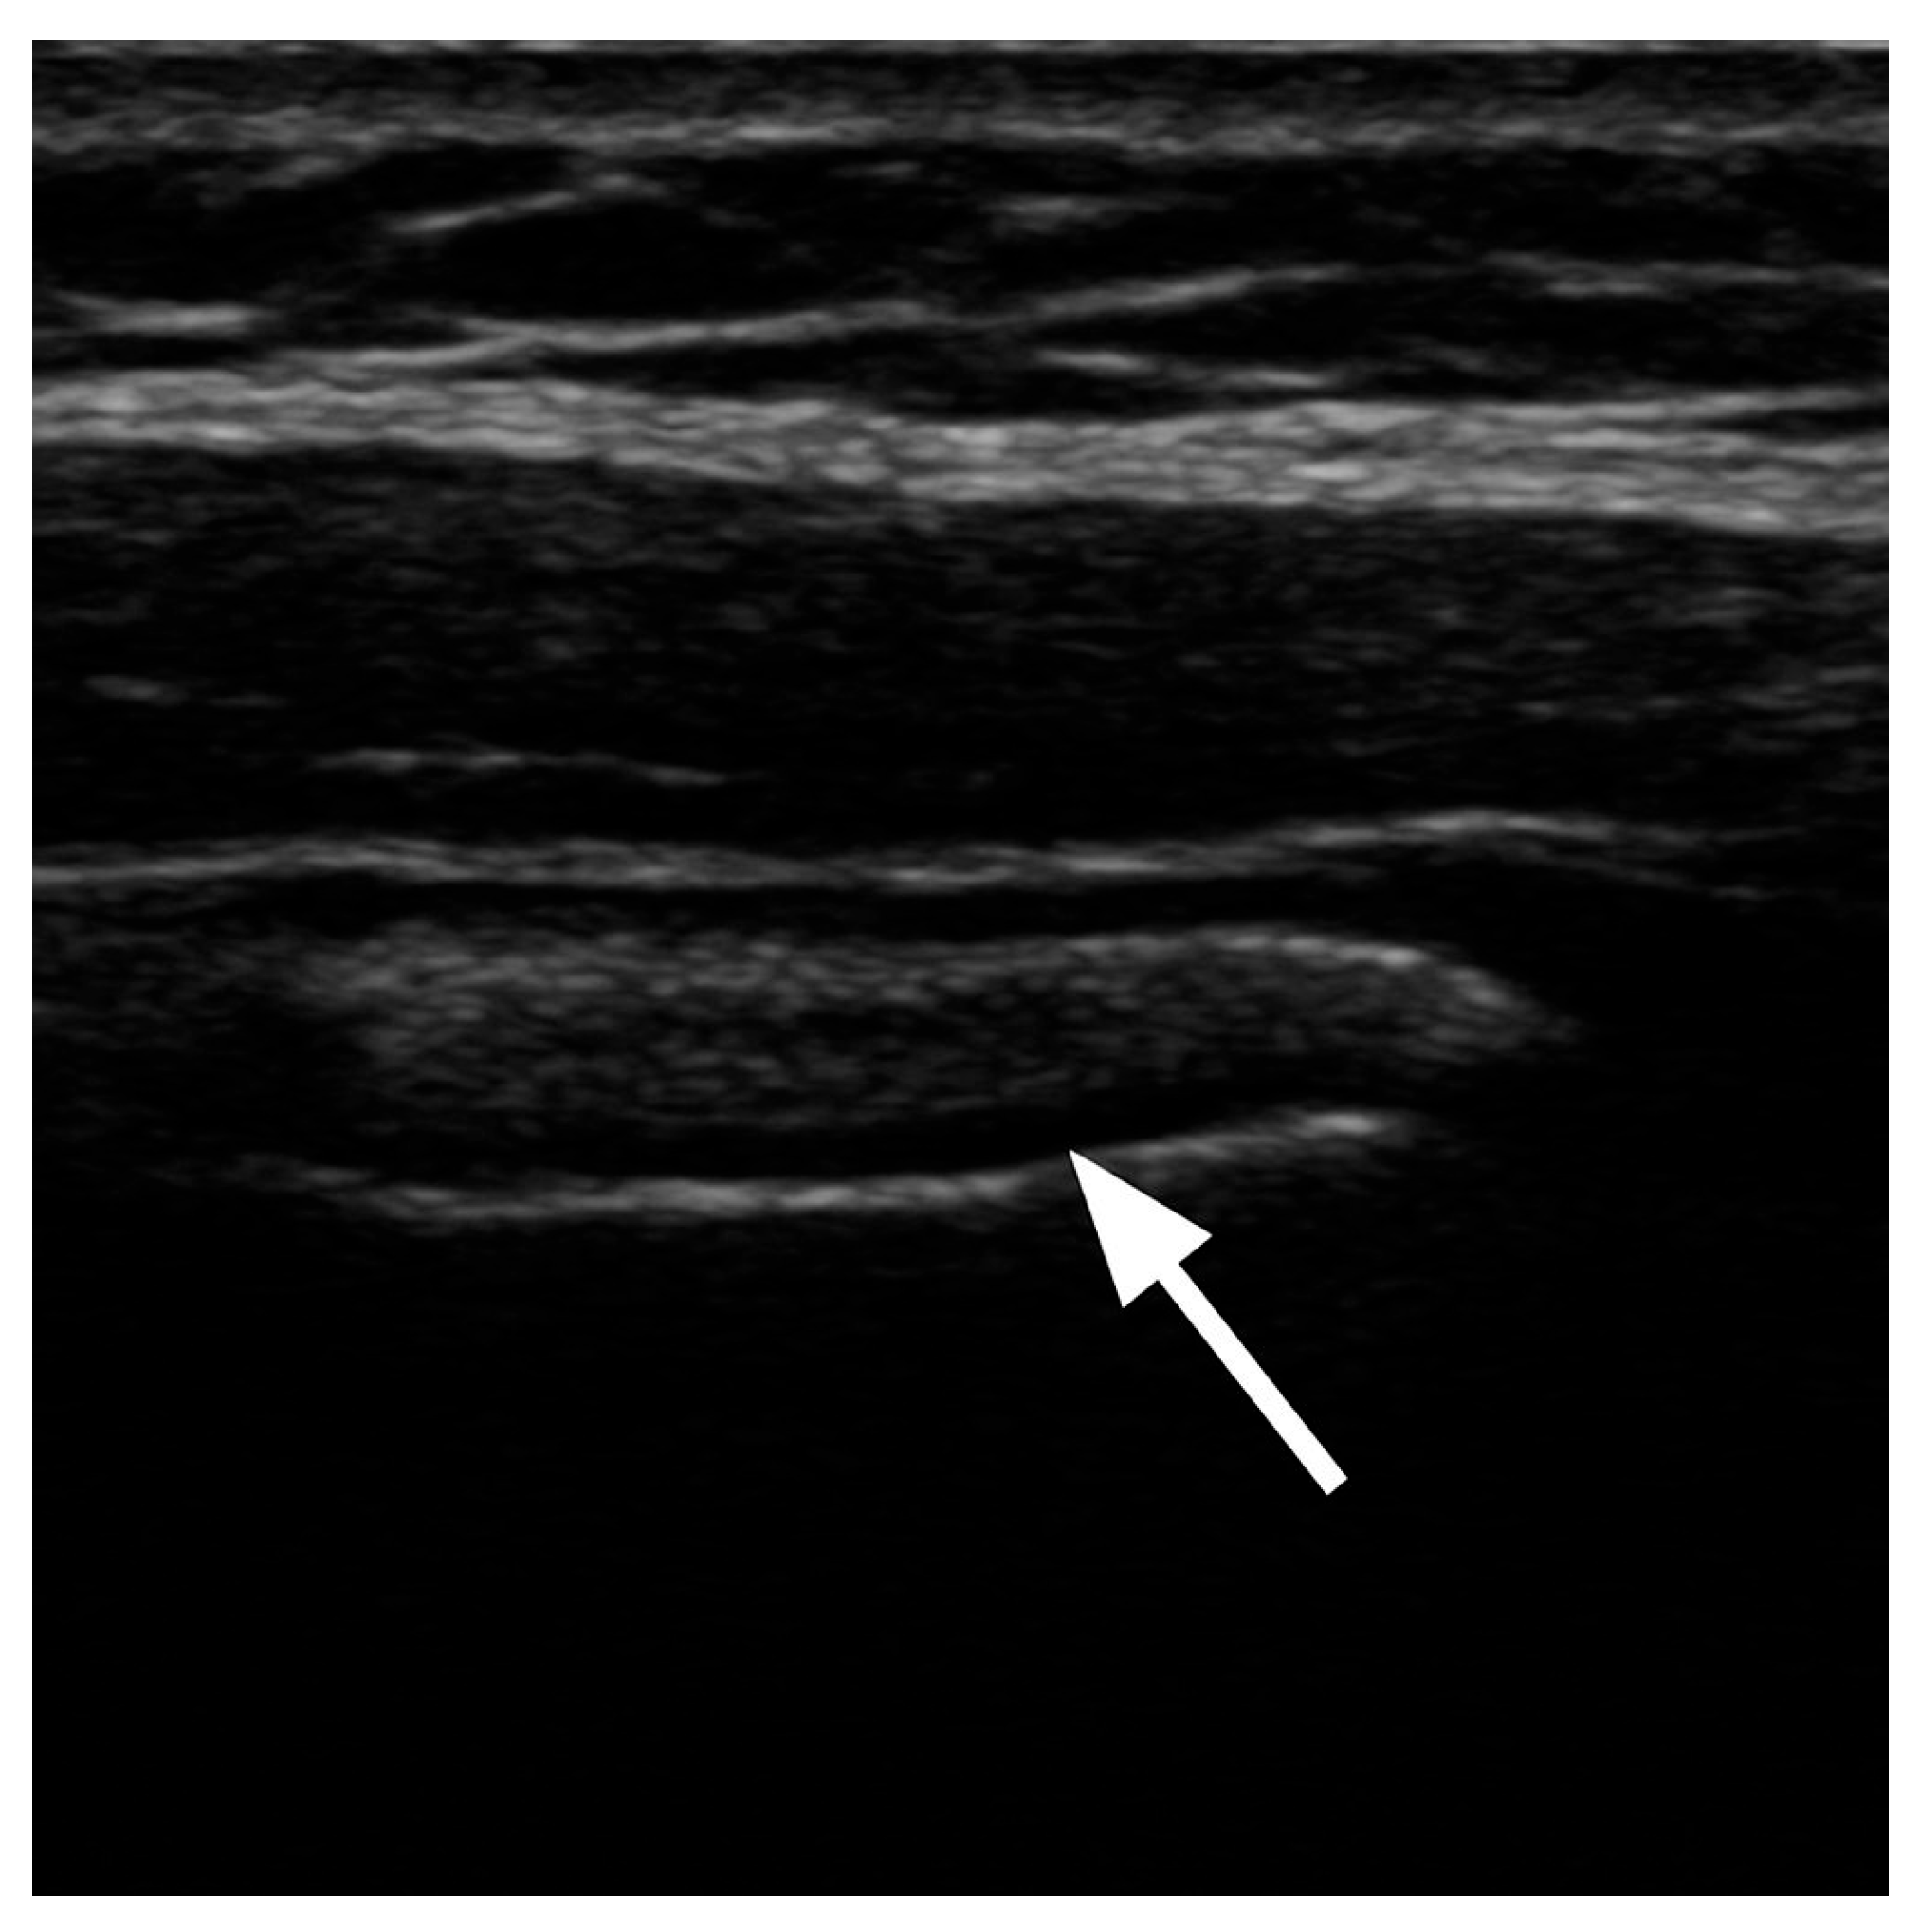

5. Visualization and Imaging Studies